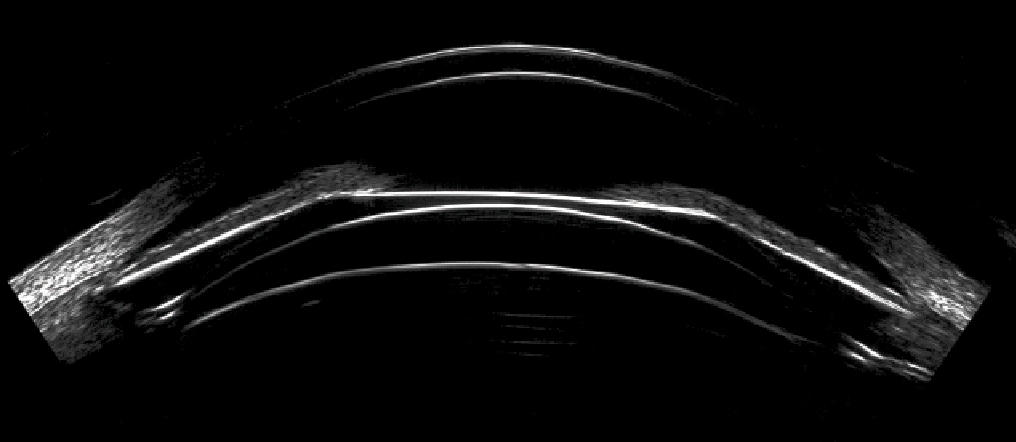

Advancements in imaging make ICL an effective option for a wider range of patients.

Phakic lenses are proving to be excellent additions to refractive practices.